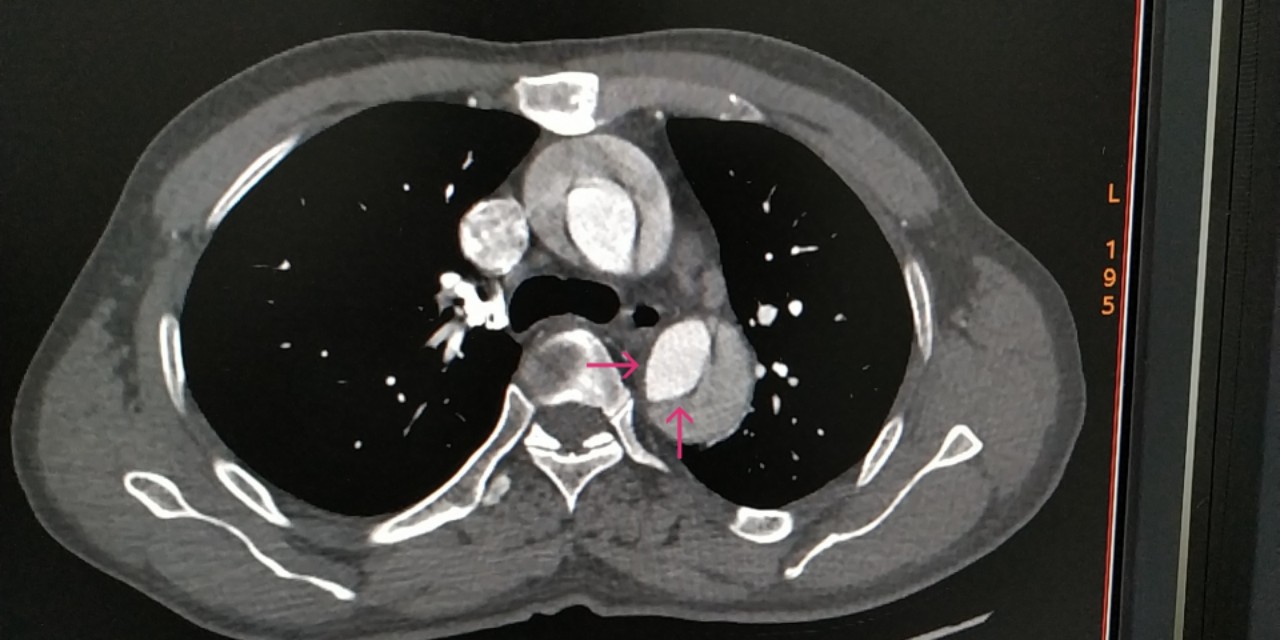

感觉不像,于是带着疑问,跟家属沟通好,我们给患者做了肺动脉和主动脉的全层CTA,发现是那个隐藏已久的杀手——主动脉夹层。而且,是全层撕裂,如下图。

咱们再聊聊主动脉夹层这个病。主动脉夹层是血管撕裂性疾病,指的是人体最大的血管主动脉内膜破裂,血流在经过破口的时候进入中膜,形成真假两腔,类似于双层水杯,类似于轮胎鼓包,这样的一种疾病。死亡风险极其高,多数病人有突发的胸痛,也可以各种症状出现,临床迷惑性极强。